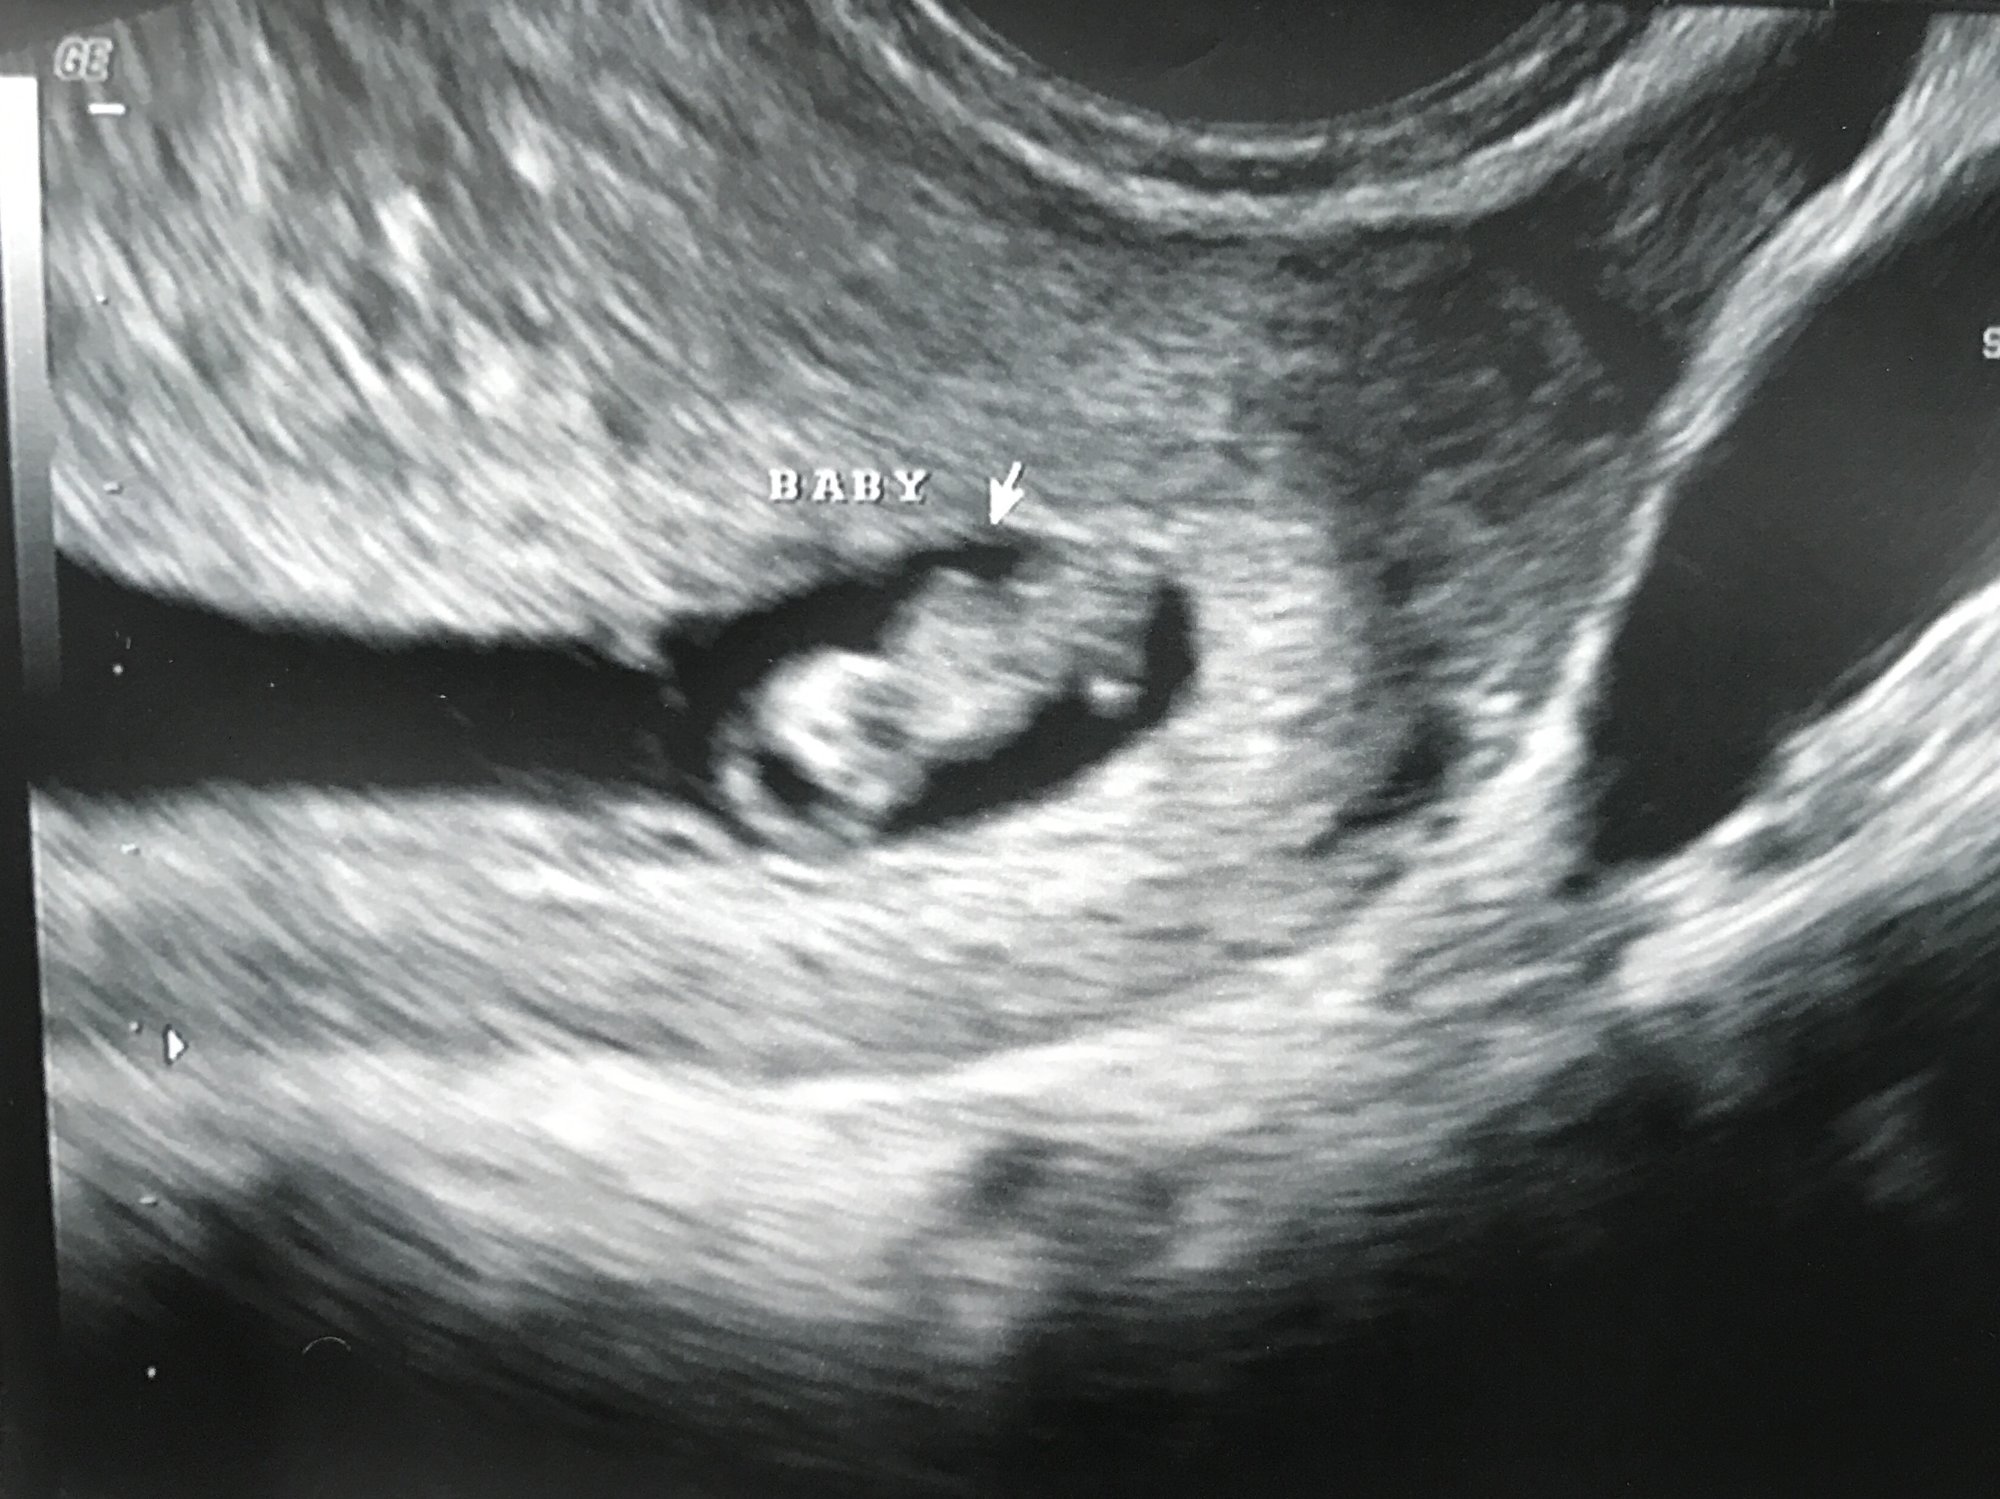

9w5d measuring at 10w1d. HR 167. Our little gummy bear was wiggling all around and even kicked for us quite a bit. They also kept bringing their hand to their mouth...it's so crazy to see what's happening inside! It's starting to look like a real human.